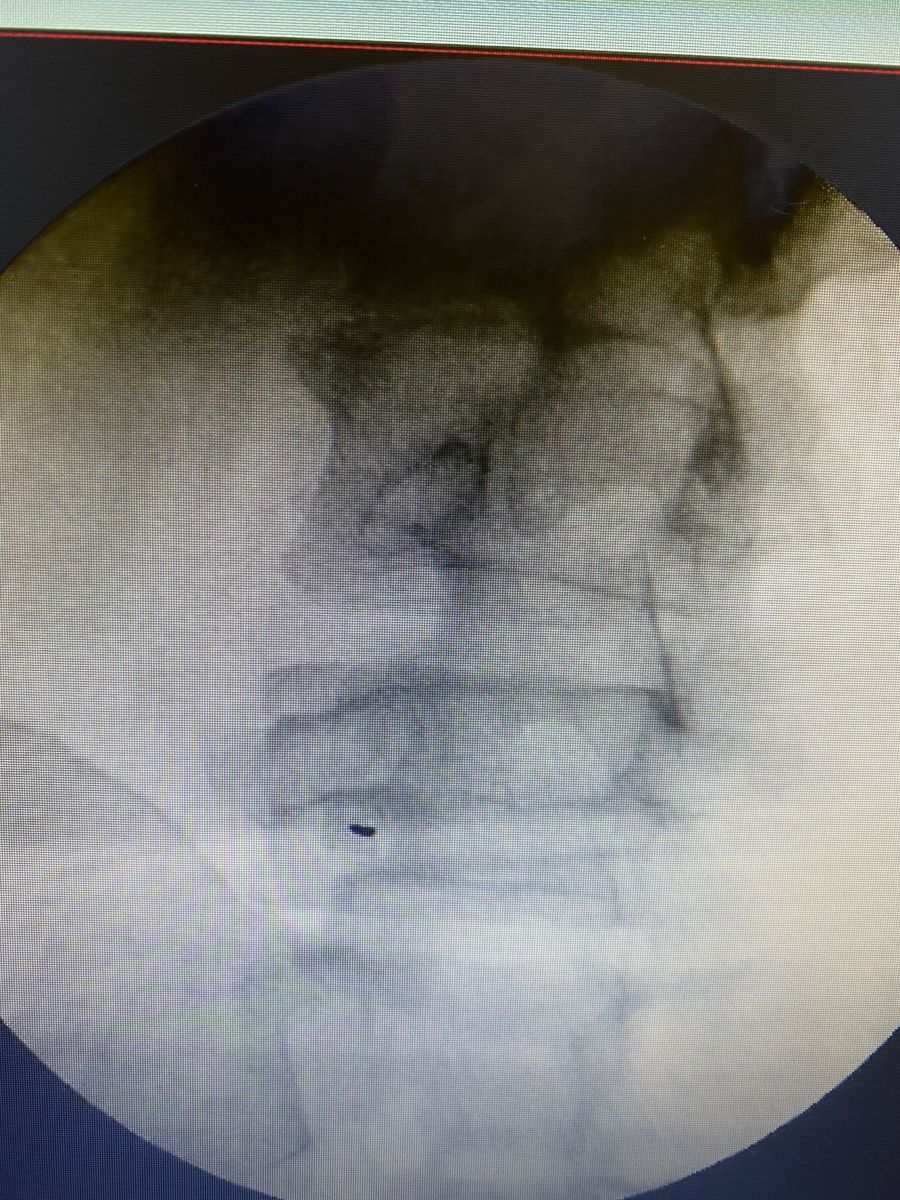

Fluoroscopia columna lumbar

Fluoroscopia: rayos X en tiempo real para ver la anatomía de la columna y planificar el punto exacto de tratamiento.